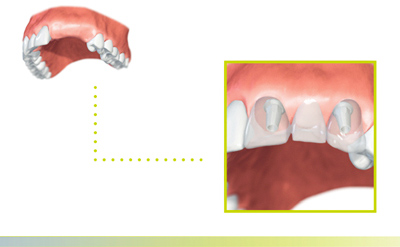

La situation

Deux dents ou plus sont absentes. Pour prévenir une perte osseuse ainsi qu’un mauvais positionnement des dents et des mâchoires, les espaces doivent être comblés aussi vite que possible, à la fois d‘un point de vue fonctionnel et d’un point de vue médical. Un bridge implantoporté est une possibilité pour combler les espaces.

L’avantage

Les dents saines voisines n’ont pas à être meulées, ce qui aide à améliorer le pronostic à long terme de ces dents. De plus, le traitement avec un implant peut aider à préserver l’os maxillaire.

Remplacement de plusieurs dents dans la région antérieure avec un bridge implantoporté

Remplacement de plusieurs dents dans la région postérieure avec un bridge implantoporté